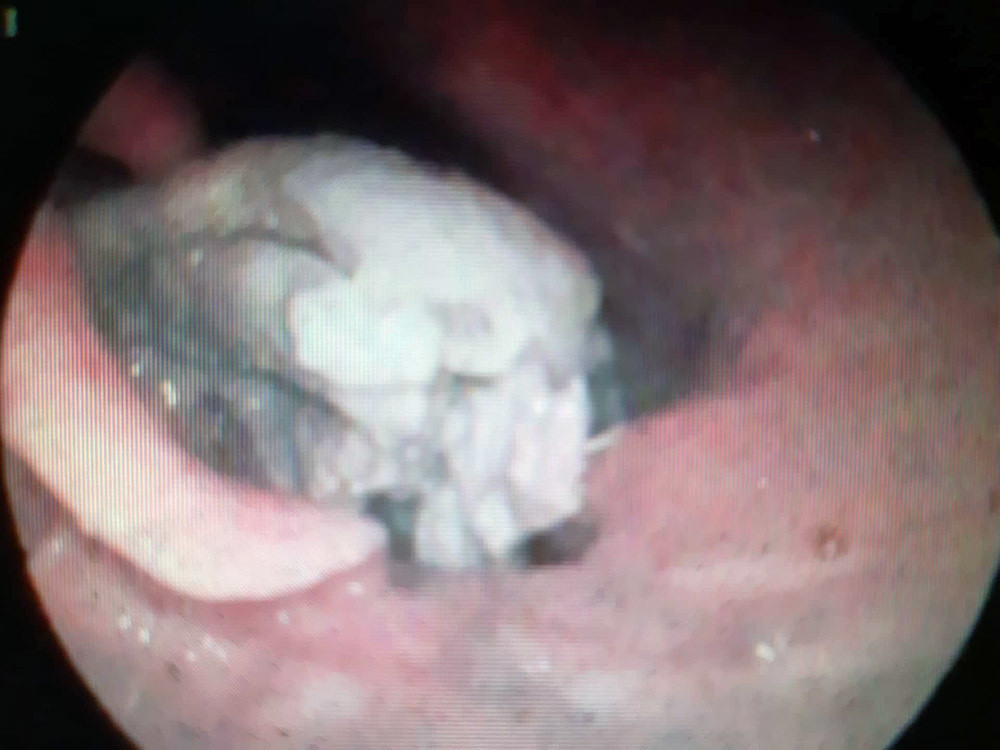

| Hình ảnh phao câu vịt xiêm nằm ở hố lê hai bên chèn ép thanh quản của bệnh nhân M. |

Sau khi thăm khám, bác sĩ đã chỉ định nội soi họng và phát hiện dị vật nằm ở hố lê hai bên chèn ép thanh quản.

Bác sỹ đã xử trí gắp dị vật ra là một cái phao câu vịt tróc da còn nguyên thịt và xương, kích thước 3cm x 3,5cm x 5cm, nằm kẹt cứng ngang hố lê hai bên, chèn ép gần hết thanh quản.

Bác sĩ Lưu cho biết: "Đây là một trường hợp đặc biệt bởi miếng phao câu vịt khá lớn đã nằm kẹt cứng vào hố lê hai bên, chèn ép thanh quản và gây khó khăn khi thực hiện thủ thuật. Chúng tôi phải xử lý cẩn thận để không làm tổn thương thực quản. Sau hơn 20 phút chúng tôi đã gắp dị vật ra khỏi thực quản bệnh nhân”.